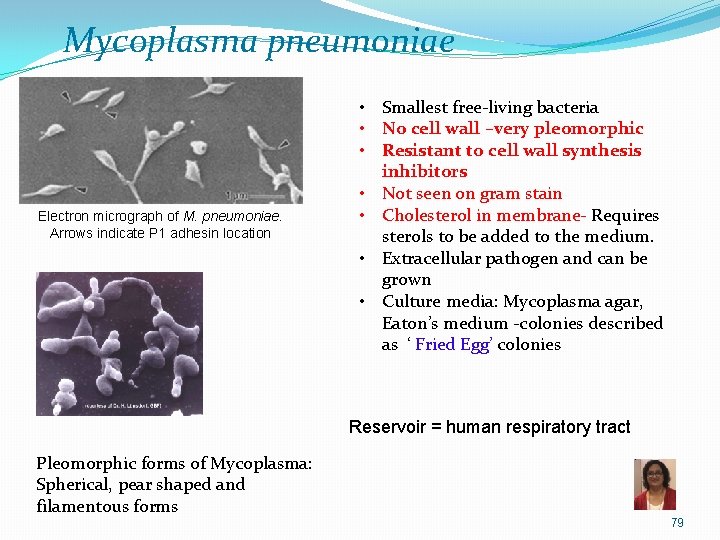

Mycoplasma pneumoniae Electron micrograph of M. pneumoniae. Arrows indicate P 1 adhesin location • Smallest free-living bacteria • No cell wall –very pleomorphic • Resistant to cell wall synthesis inhibitors • Not seen on gram stain • Cholesterol in membrane- Requires sterols to be added to the medium. • Extracellular pathogen and can be grown • Culture media: Mycoplasma agar, Eaton’s medium -colonies described as ‘ Fried Egg’ colonies Reservoir = human respiratory tract Pleomorphic forms of Mycoplasma: Spherical, pear shaped and filamentous forms 79